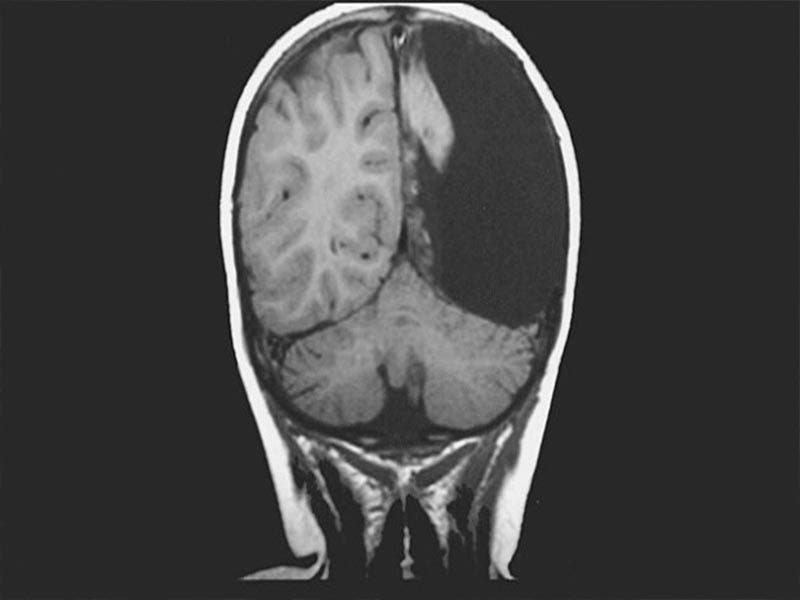

Hombre vive solo con la mitad de su cerebro.- Médicos en Rusia descubrieron a través de una tomografía de la cabeza de ex soldado; que el hombre ha vivido más de 60 años solo con la mitad de su cerebro.

El exsoldado ingresó al hospital debido a que tenía trastornos circulatorios, sin embargo después de un análisis los especialistas se dieron cuenta que el hombre tenía un “agujero negro” en su hemisferio izquierdo.

Los médicos se sorprendieron al ver que la mitad del cerebro del paciente tenía un agujero negro, sin embargo el exsoldado nunca tuvo problemas motores ni visuales por lo que siempre llevó una vida normal sin la mitad de su cerebro.

Los médicos indicaron que el caso del exsoldado es único, debido a que se trata de una falla congénita, por lo que ahora “si un hemisferio está dañado o no desarrollado, el segundo asume completamente las funciones de ambos”.